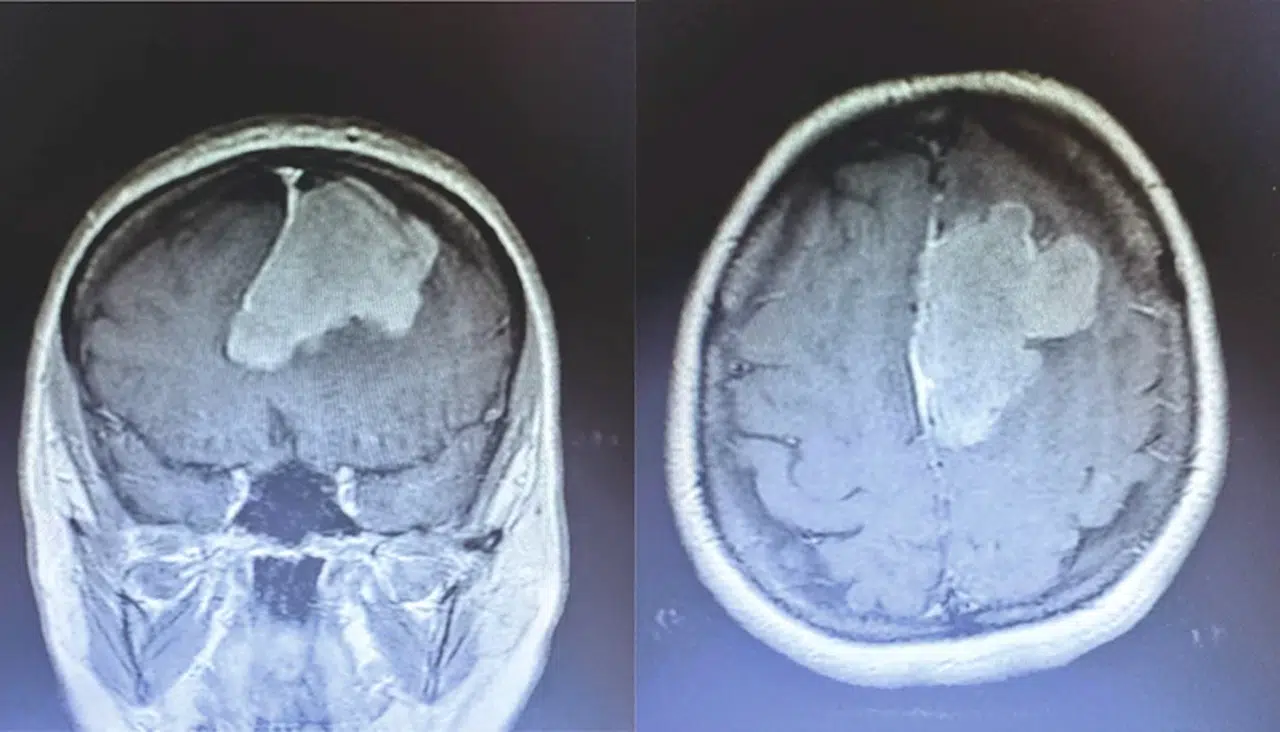

Erbaa'da beyin tümörü ameliyatı yapıldı

TOKAT (AA) - Tokat'ın Erbaa ilçesinde beyin tümör ameliyatı gerçekleştirildi.

İl Sağlık Müdürlüğünden yapılan yazılı açıklamaya göre, Ayfer Polat, rahatsızlığı sebebiyle Erbaa Devlet Hastanesi Beyin ve Sinir Hastalığı servisine başvurdu.

Yapılan tetkiklerde Polat'ın ameliyat olması gerektiği belirlendi.

Polat'ın nöronavigasyon eşliğinde mikroskopik yaklaşımla beyin tümörü ameliyatı, Erbaa Devlet Hastanesinde yapıldı.

Hastanede ikinci kez yapılan ameliyat, beyin ve sinir cerrahisi uzmanı operatör Dr. Ali Kalpan tarafından gerçekleştirildi.